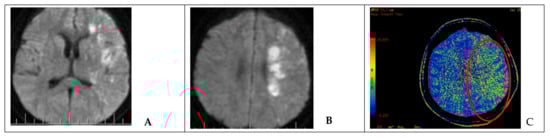

Figure 3. Neuroimaging in a patient after endovascular occlusion of the ICA (clinical case 5). (A,B) MRI of the brain (DWI); an area of acute ischemic injury in the left hemisphere (hyperintense area) can be visualized. (C) MSCT-perfusion study demonstrating signs of cerebral circulation insufficiency in the form of prolonged blood transit time in the basin of the left MCA (red circled area).

Hemiparesis occurred in one case with sufficient collateral circulation after occlusion of the injured ICA. After endovascular intervention, DWI MRI and MSCT-perfusion images showed a decrease in the cerebral blood flow and ischemic zone in the middle cerebral artery (MCA) territory on the side of the occluded ICA (Figure 3). Therefore, the patient underwent single-barrel extra-intracranial anastomosis between the superficial temporal artery and the middle cerebral artery on the left side.